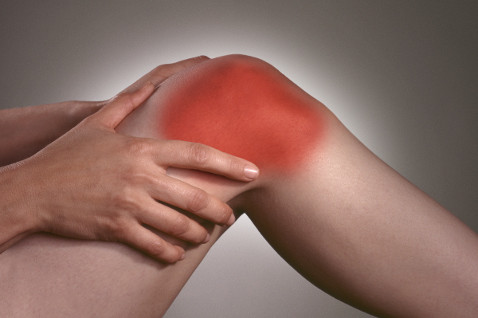

Если воспалился сустав на ноге, то заметить это возможно по внешнему показателю. Значительно меняется внешний вид сустава нижней конечности. Пораженное соединение отечное, горячее на ощупь, кожный покров имеет блеск, покрасневшее.

- отек;

- боль;

- покраснение локализованного места;

- ограничение подвижности;